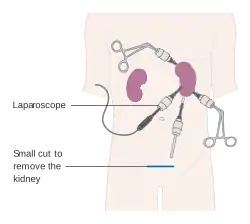

The surgery is performed with the patient under general anesthesia. A kidney can be removed through an open incision or by laparoscopic surgery. For the open procedure, the surgeon makes an incision in the side of the abdomen to reach the kidney. Depending on circumstances, the incision can also be made midline. The ureter and blood vessels are disconnected, and the kidney is then removed. The laparoscopic approach utilizes three or four small (5–10 mm) cuts in the abdominal and flank area. The kidney is completely detached inside the body and then placed in a bag. One of the incisions is then expanded to remove the kidney for cancer operations. If the kidney is being removed for other causes, it can be morcellated and removed through the small incisions. Recently, this procedure is performed through a single incision in the patient's navel. This advanced technique is called single port laparoscopy.